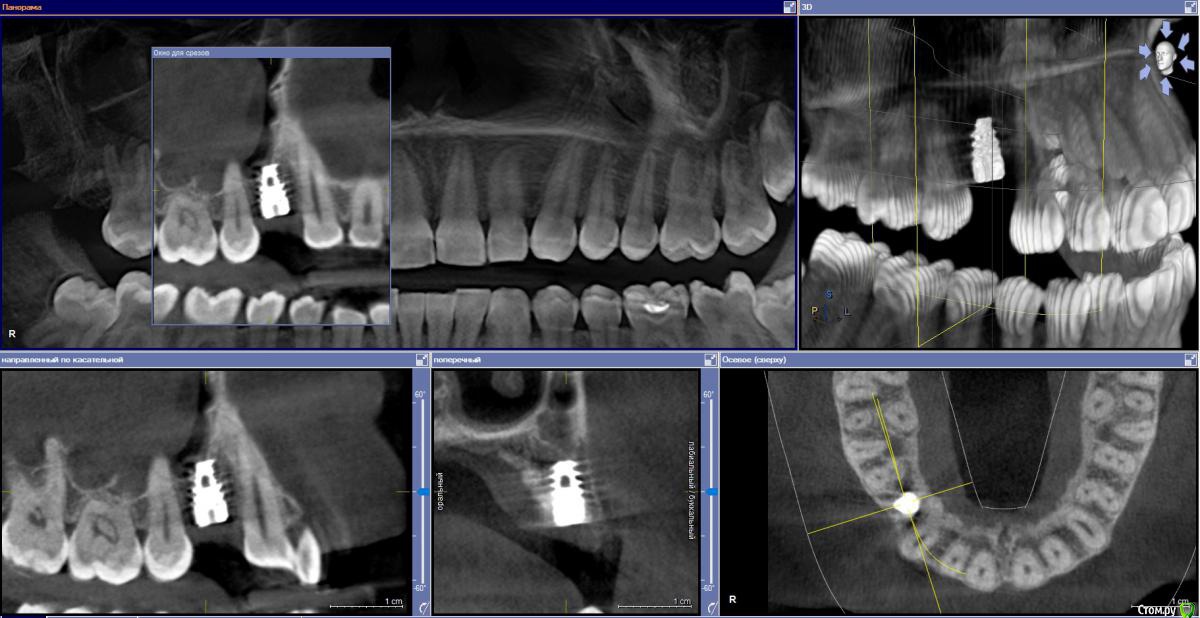

Ponchik Опубликовано 1 августа, 2017 Автор Поделиться Опубликовано 1 августа, 2017 Так и не состоялся тот случай, но сразу же пришла другая пациентка с подобной проблемой. (Проблема в докторе не делающем синус-лифтинга)Планирование Что получилось сразу Формирователь через 3 месяца Ставил AB SPI 4.2 - 8 Фрезой до 6мм, далее вогнутым остеотомом. Изменений в звуке не заметил. Достучал до ограничителя и все.Что в пазухе проблемы увидел, только потом на КТ после имплантации.Всё.Кидайте тапками.P.S.Это был первый имплант на верхней челюсти. Ссылка на комментарий

kamranchick Опубликовано 1 августа, 2017 Поделиться Опубликовано 1 августа, 2017 Так и не состоялся тот случай, но сразу же пришла другая пациентка с подобной проблемой. (Проблема в докторе не делающем синус-лифтинга)Планированиедо.jpg Что получилось сразупосле.jpg Формирователь через 3 месяца 3ме.jpg3мес.jpg Ставил AB SPI 4.2 - 8 Фрезой до 6мм, далее вогнутым остеотомом. Изменений в звуке не заметил. Достучал до ограничителя и все.Что в пазухе проблемы увидел, только потом на КТ после имплантации.Всё.Кидайте тапками.P.S.Это был первый имплант на верхней челюсти.если жалоб нет то все ок Ссылка на комментарий